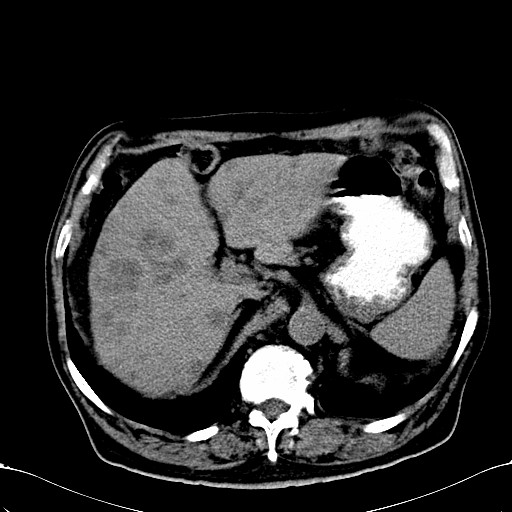

标题: CT28270:胰管扩张,肝多发占位 [打印本页]

标题: CT28270:胰管扩张,肝多发占位

患者,男,75岁。

肝脏多方低密度结节,边缘模糊,考虑多发转移,胰管明显扩张,建议增强扫描钩突情况

肝脏多发低密度灶,胰头似呈低密度,胰管扩张,建议增强,

胰管显著扩张,但胆总管未见扩张征象,不太符合胰头占位!考虑慢性胰腺炎.胃窦占位并肝内转移可能!mrcp胃镜增强一起上!